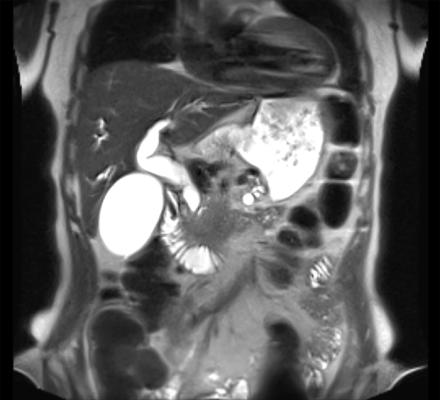

To address the aforementioned challenge, the Tsukuba team has created a predictive model by integrating radiomics features extracted from CT and MRI images using artificial intelligence deep-learning techniques. This model has demonstrated an 89% success rate in predicting lymph node metastasis, a rate that rises to 91% when the model is validated with data from an external hospital. Furthermore, the performance of the model remains consistent, irrespective of the tumor size being larger or smaller than 2 cm.